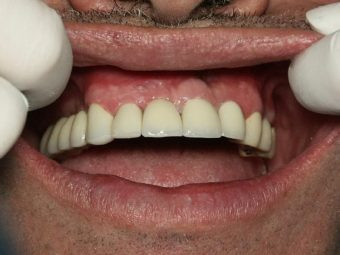

Final, Coronas de Porcelana

Inicial